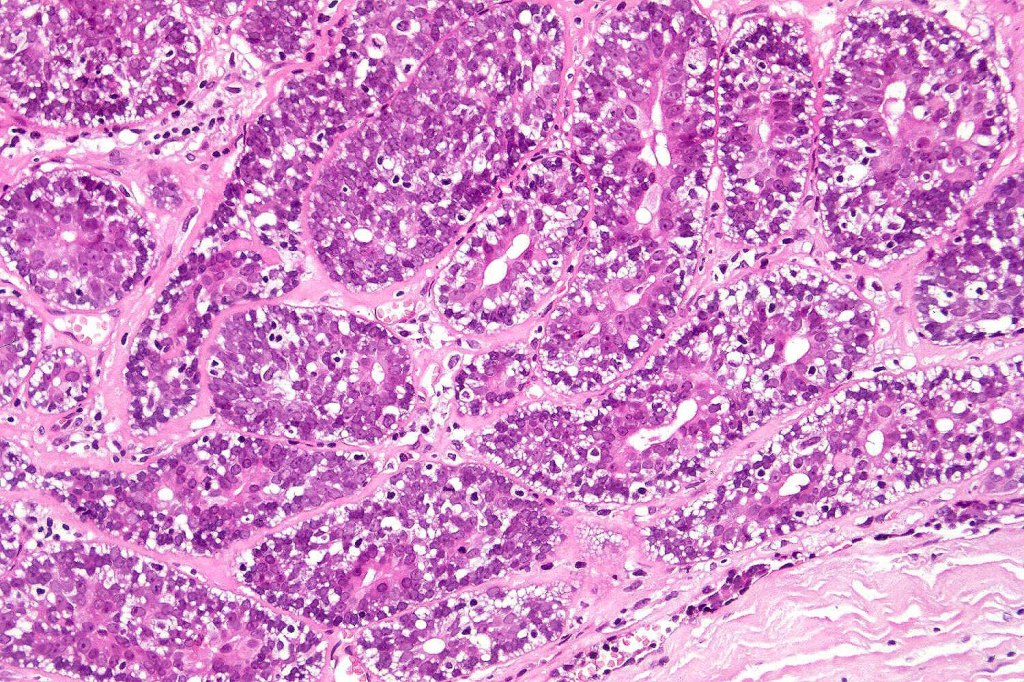

Histological features

•Pre-existent spiradenoma

•Malignant component shows loss of dual cell population, increased mitotic activity, atypical mitoses & necrosis

•Perineural infiltration & LVI may be present

•1. Salivary gland type basal cell adenocarcinoma-like pattern, low grade (BCAC-LG)